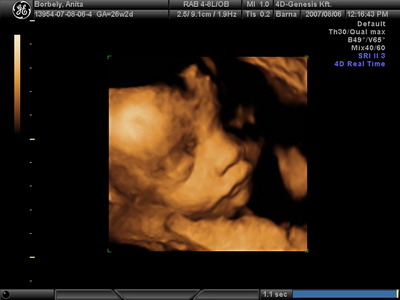

És egy tappancs 2008.03.08 19:45